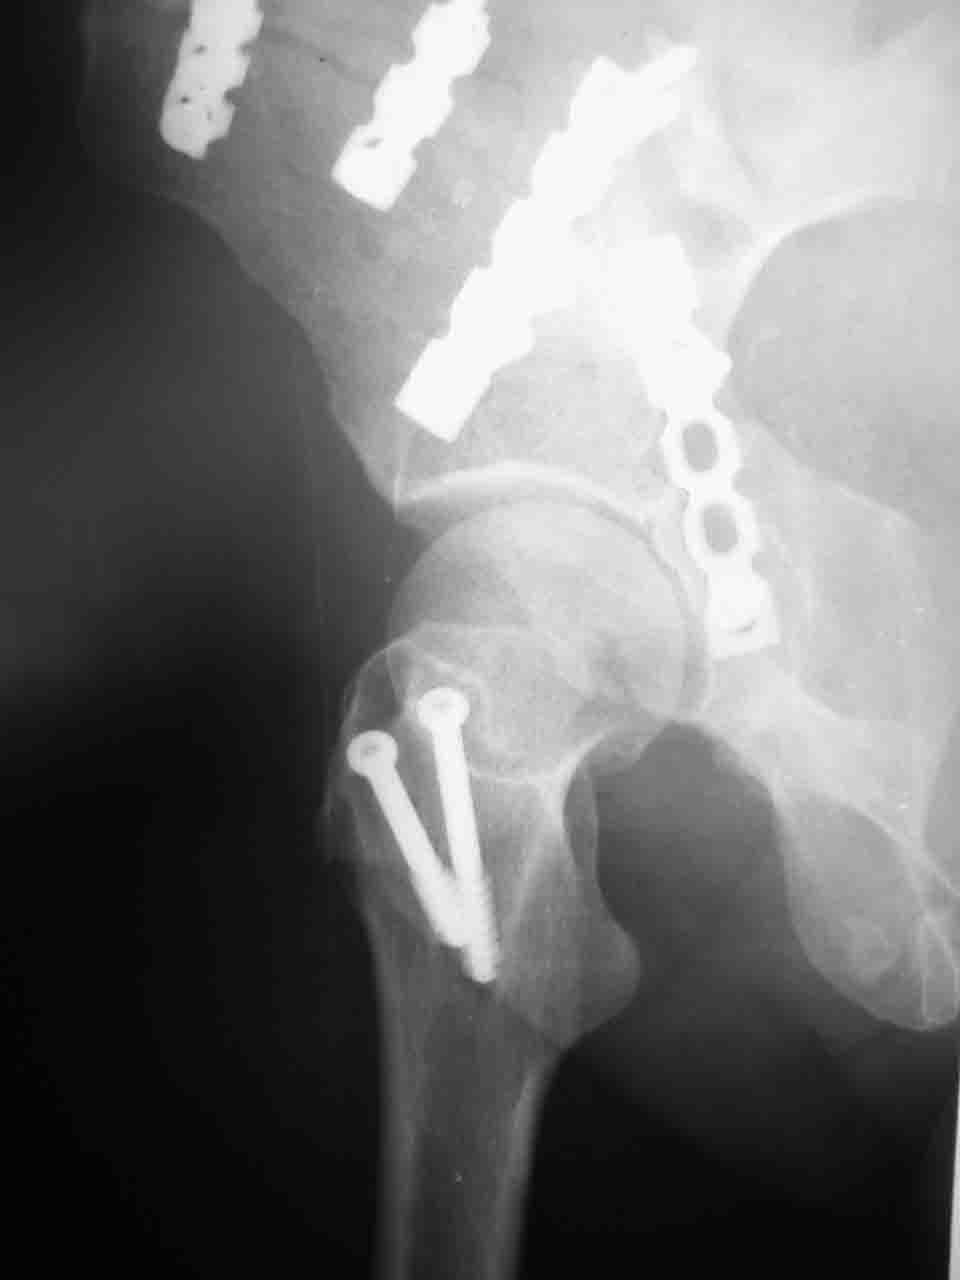

Сложностью, ассоциативностью характера перелома, я бы с радостью воспользовался мининвазивной перкутанной фиксацией винтами, но боюсь, что результат был бы ещё хуже, техникой непрямой репозиции перелома не владею, поэтому пытаясь получить анатомичную впадину приходится широко открывать, по крайней мере пока, а дальше буду пытаться уменьшать пространство...

Илеофеморальный доступ не совсем передний и сравнительно с илеоингвинальным, и Кохера-Лангенбека открывает весь наружный таз кроме самых передних отделов лонных костей, фиксацию которых я не ставил в задачу. Обширность диссекции, большая длительность операции и более высокий риск гетерооссификации - отрицательные моменты в обмен на возможность легче ориентироваться.

Комбинированные доступы - хорошая альтернатива, меньший процент осложнений, но я заметил , что без сбора *мозаики* безымянной кости сложно отрепонировать переднюю колонну, а с нерепонированной передней колонной невозможно анатомично собрать заднюю колонну и соотв. фрагменты стенки - так.что все равно открывать придется широко. Поэтому выбирая комбинированный

подход, передний доступ должен был бы быть продлен до задней трети крыла безымянной кости, а задний - практически до того же уровня, оставляя 6-7 см мостик. При этом вместо одного послеоп. рубца у больного остаются два сравнительно длинных.

Вопрос доступа к вертлужной впадине при остеосинтезе задача не простая. Конечно, у Летурнеля и Тайла всё давно описано, нам остается только брать на вооружение. Но сами понимаете, что не бывает двух одинаковых ситуаций, поэтому в каждом случае вопрос решается сугубо индивидуально. Наша главная цель - восстановить анатомию с нанесением минимальной дополнительной травмы тазобедреннному суставу, думаю с этим никто не поспорит. Расширенный илиофеморальный доступ уж слишком травматичен (как сказал один коллега "таз лежит отдельно, больной отдельно").Стоит ли делать из пациента анатомический препарат для того чтобы легче ориентироваться. Да и нужно ли собирать всю "мозаику"? Мы применяли при таких операциях своеобразную операционную хитрость - сначала устраняли грубое смещение крыла под гребнем с фиксацией так называемой "плавающей" пластиной (временно фиксированной на двух винтах)- доступ или продлевали боковой, или делали небольшой дополнительный разрез над гребнем. Это позволяло устранить грубое смещение и захождение отломков тела повздошной кости, что значительно облегчало репозицию и остеосинтез впадины над сводом. Основное внимание конечно же уделяли нагружаемому задне-верхнему отделу. Сообщите ваш адрес, пришлю схемы и рентгенограммы.